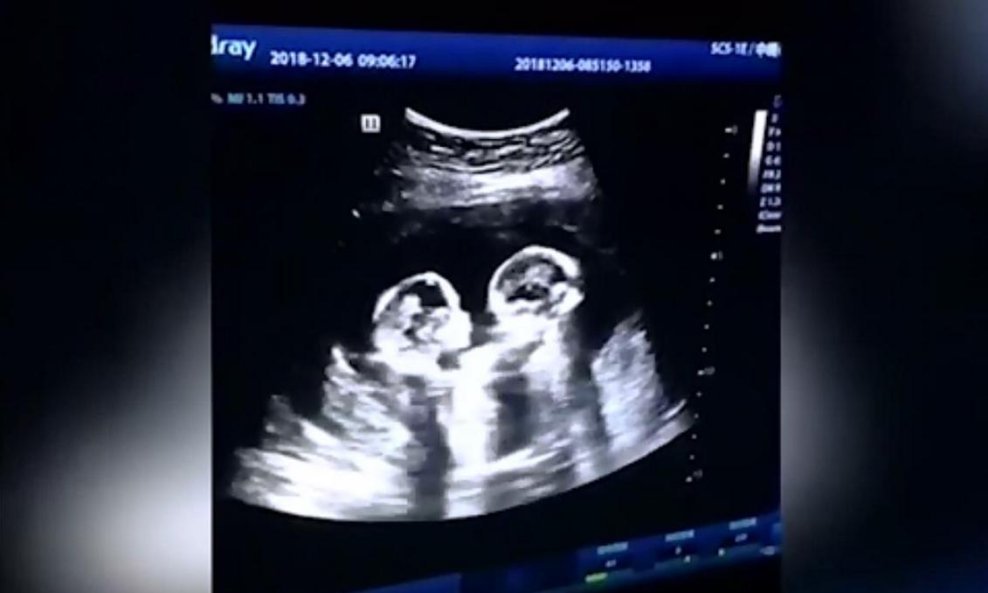

Kad je Kinez iz Yinchuana po imenu Tao vidio ultrazvuk svojih blizanki ostao je bez teksta – njegove su se nerođene djevojčice, činilo mu se, potukle!

Budući otac nije mogao vjerovati kad je na ultrazvuku svoje trudne žene ugledao prvu tuču svoje buduće djece. Prema riječima liječnika bolnice u Yinchuanu u Kini, iako je scena nasmijala oca, u pitanju je potencijalno opasni i prilično rijedak slučaj kad blizanke u utrobi ne rastu odvojeno već zajedno.

Srećom, trudnoća je prošla dobro i četiri mjeseca nakon ultrazvuka blizanke Jagoda i Trešnja rodile su se potpuno zdrave.